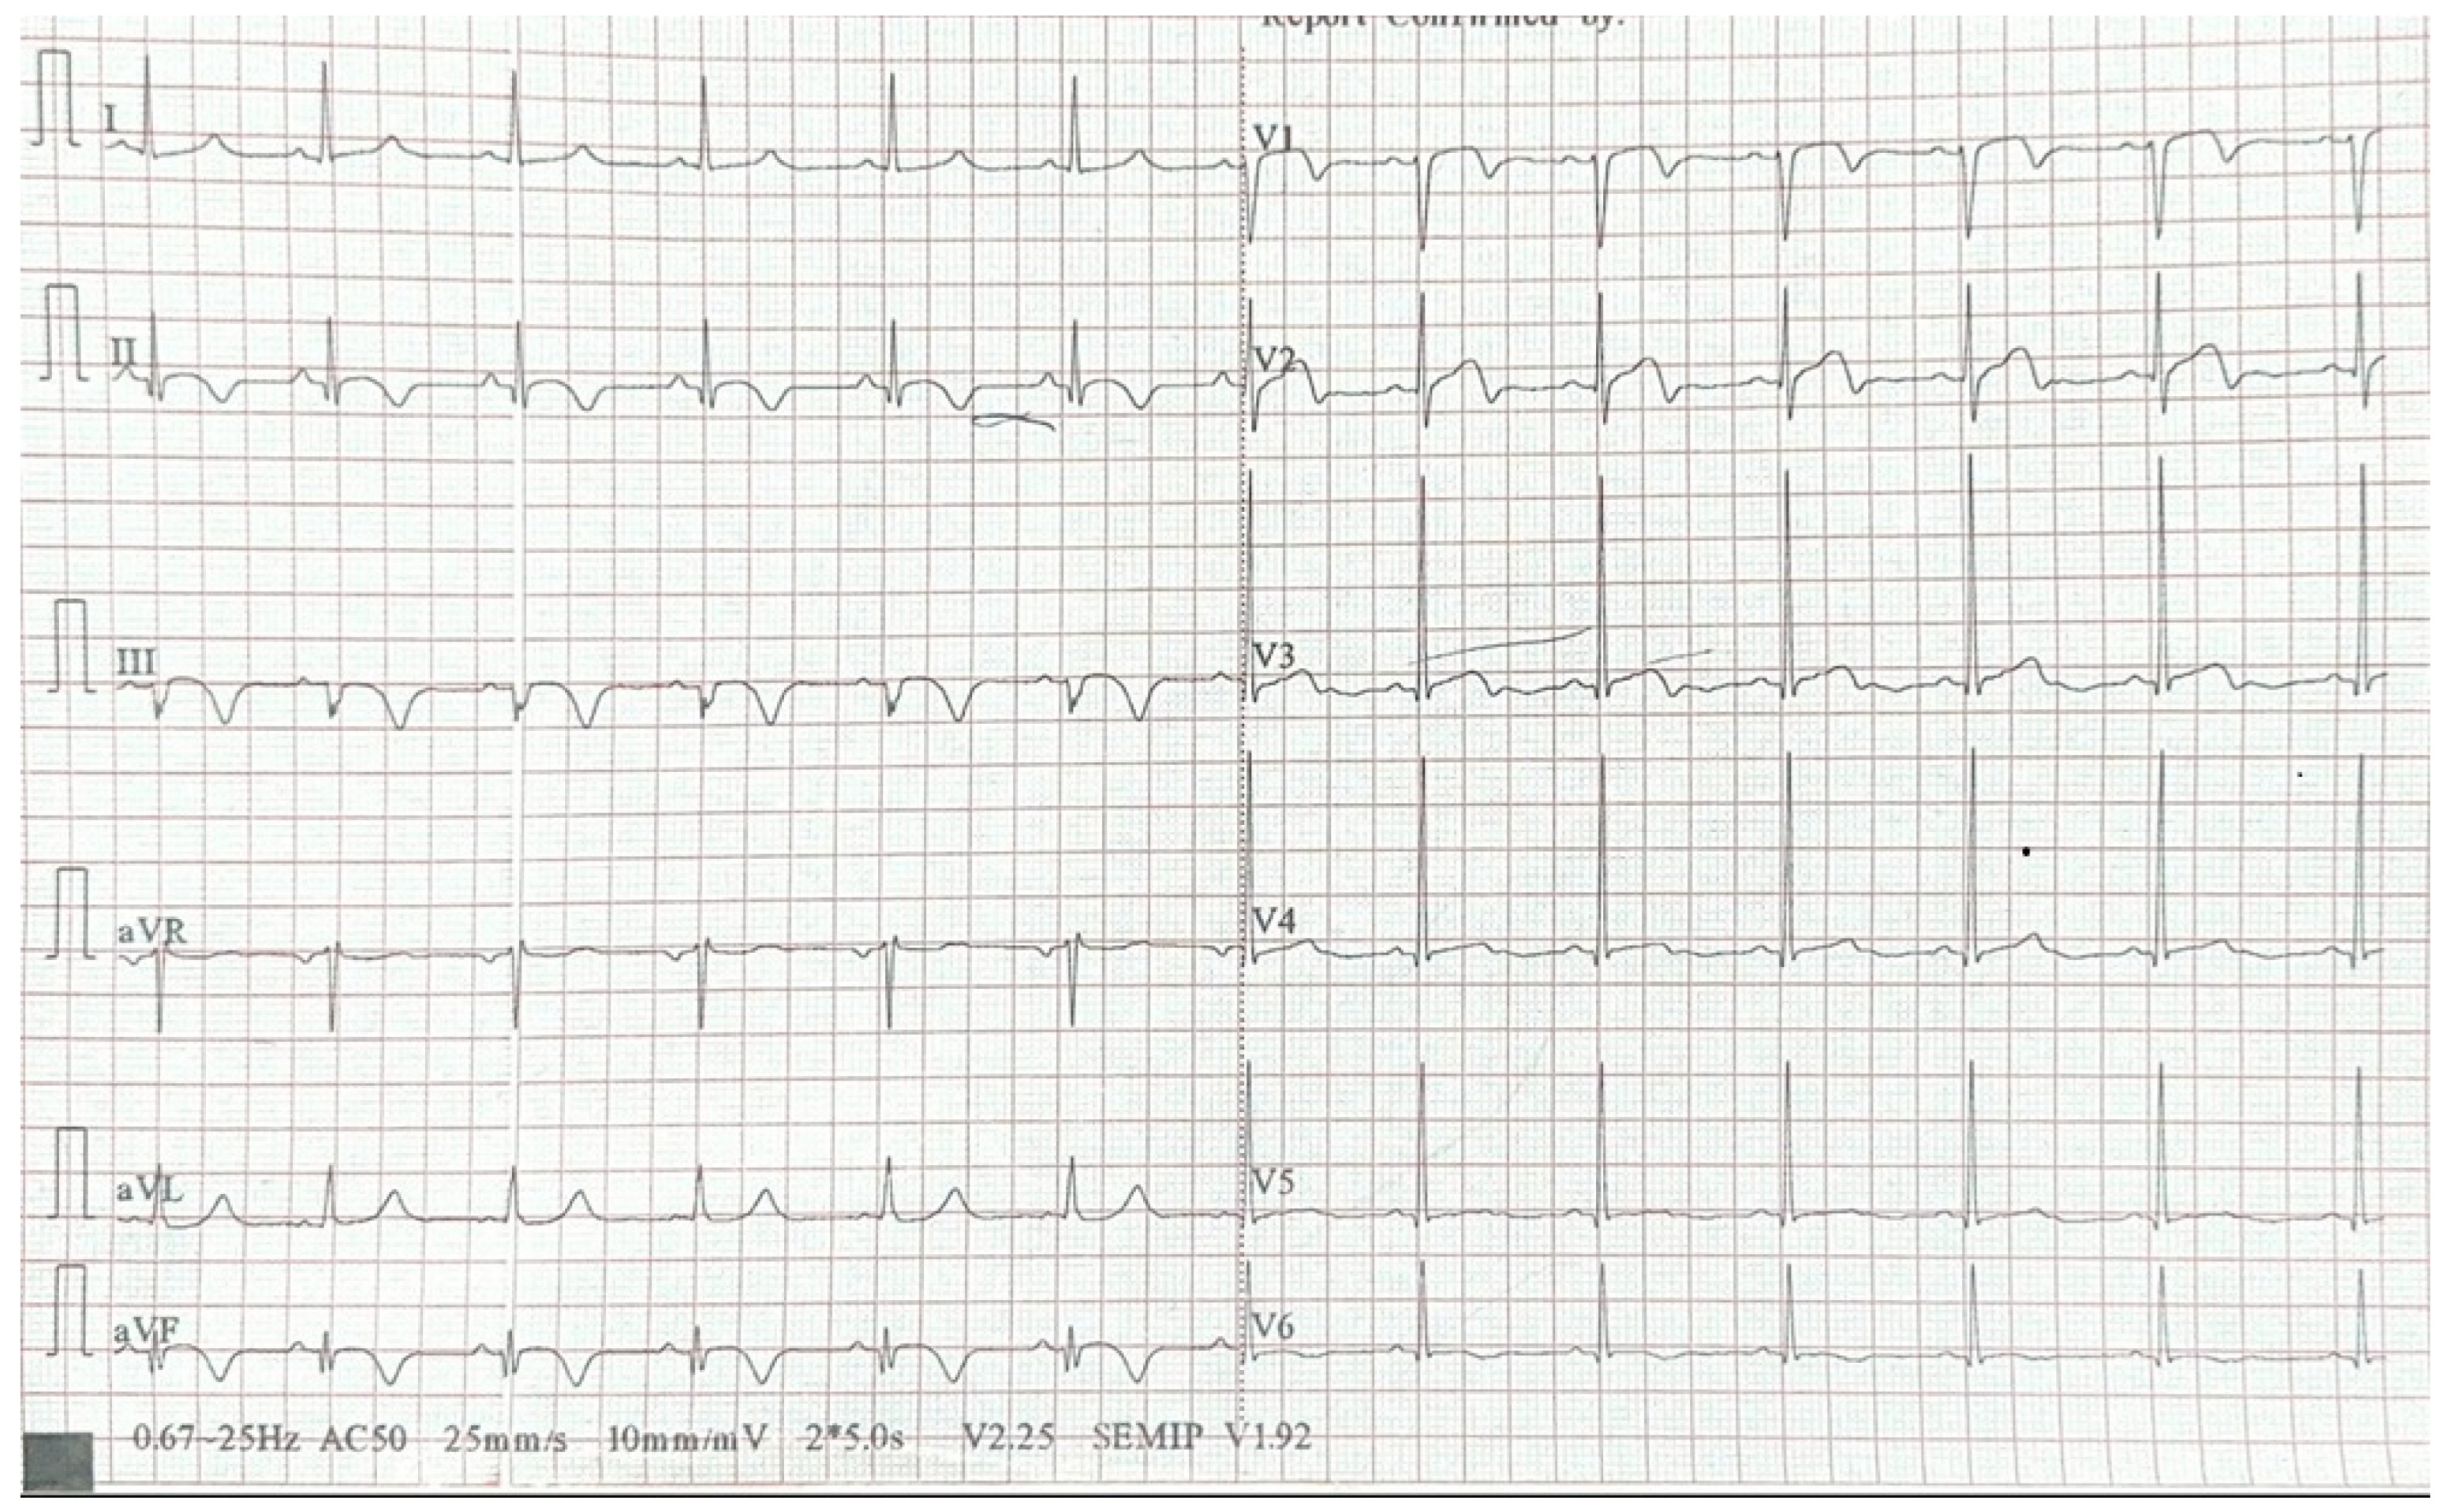

2. Case Report